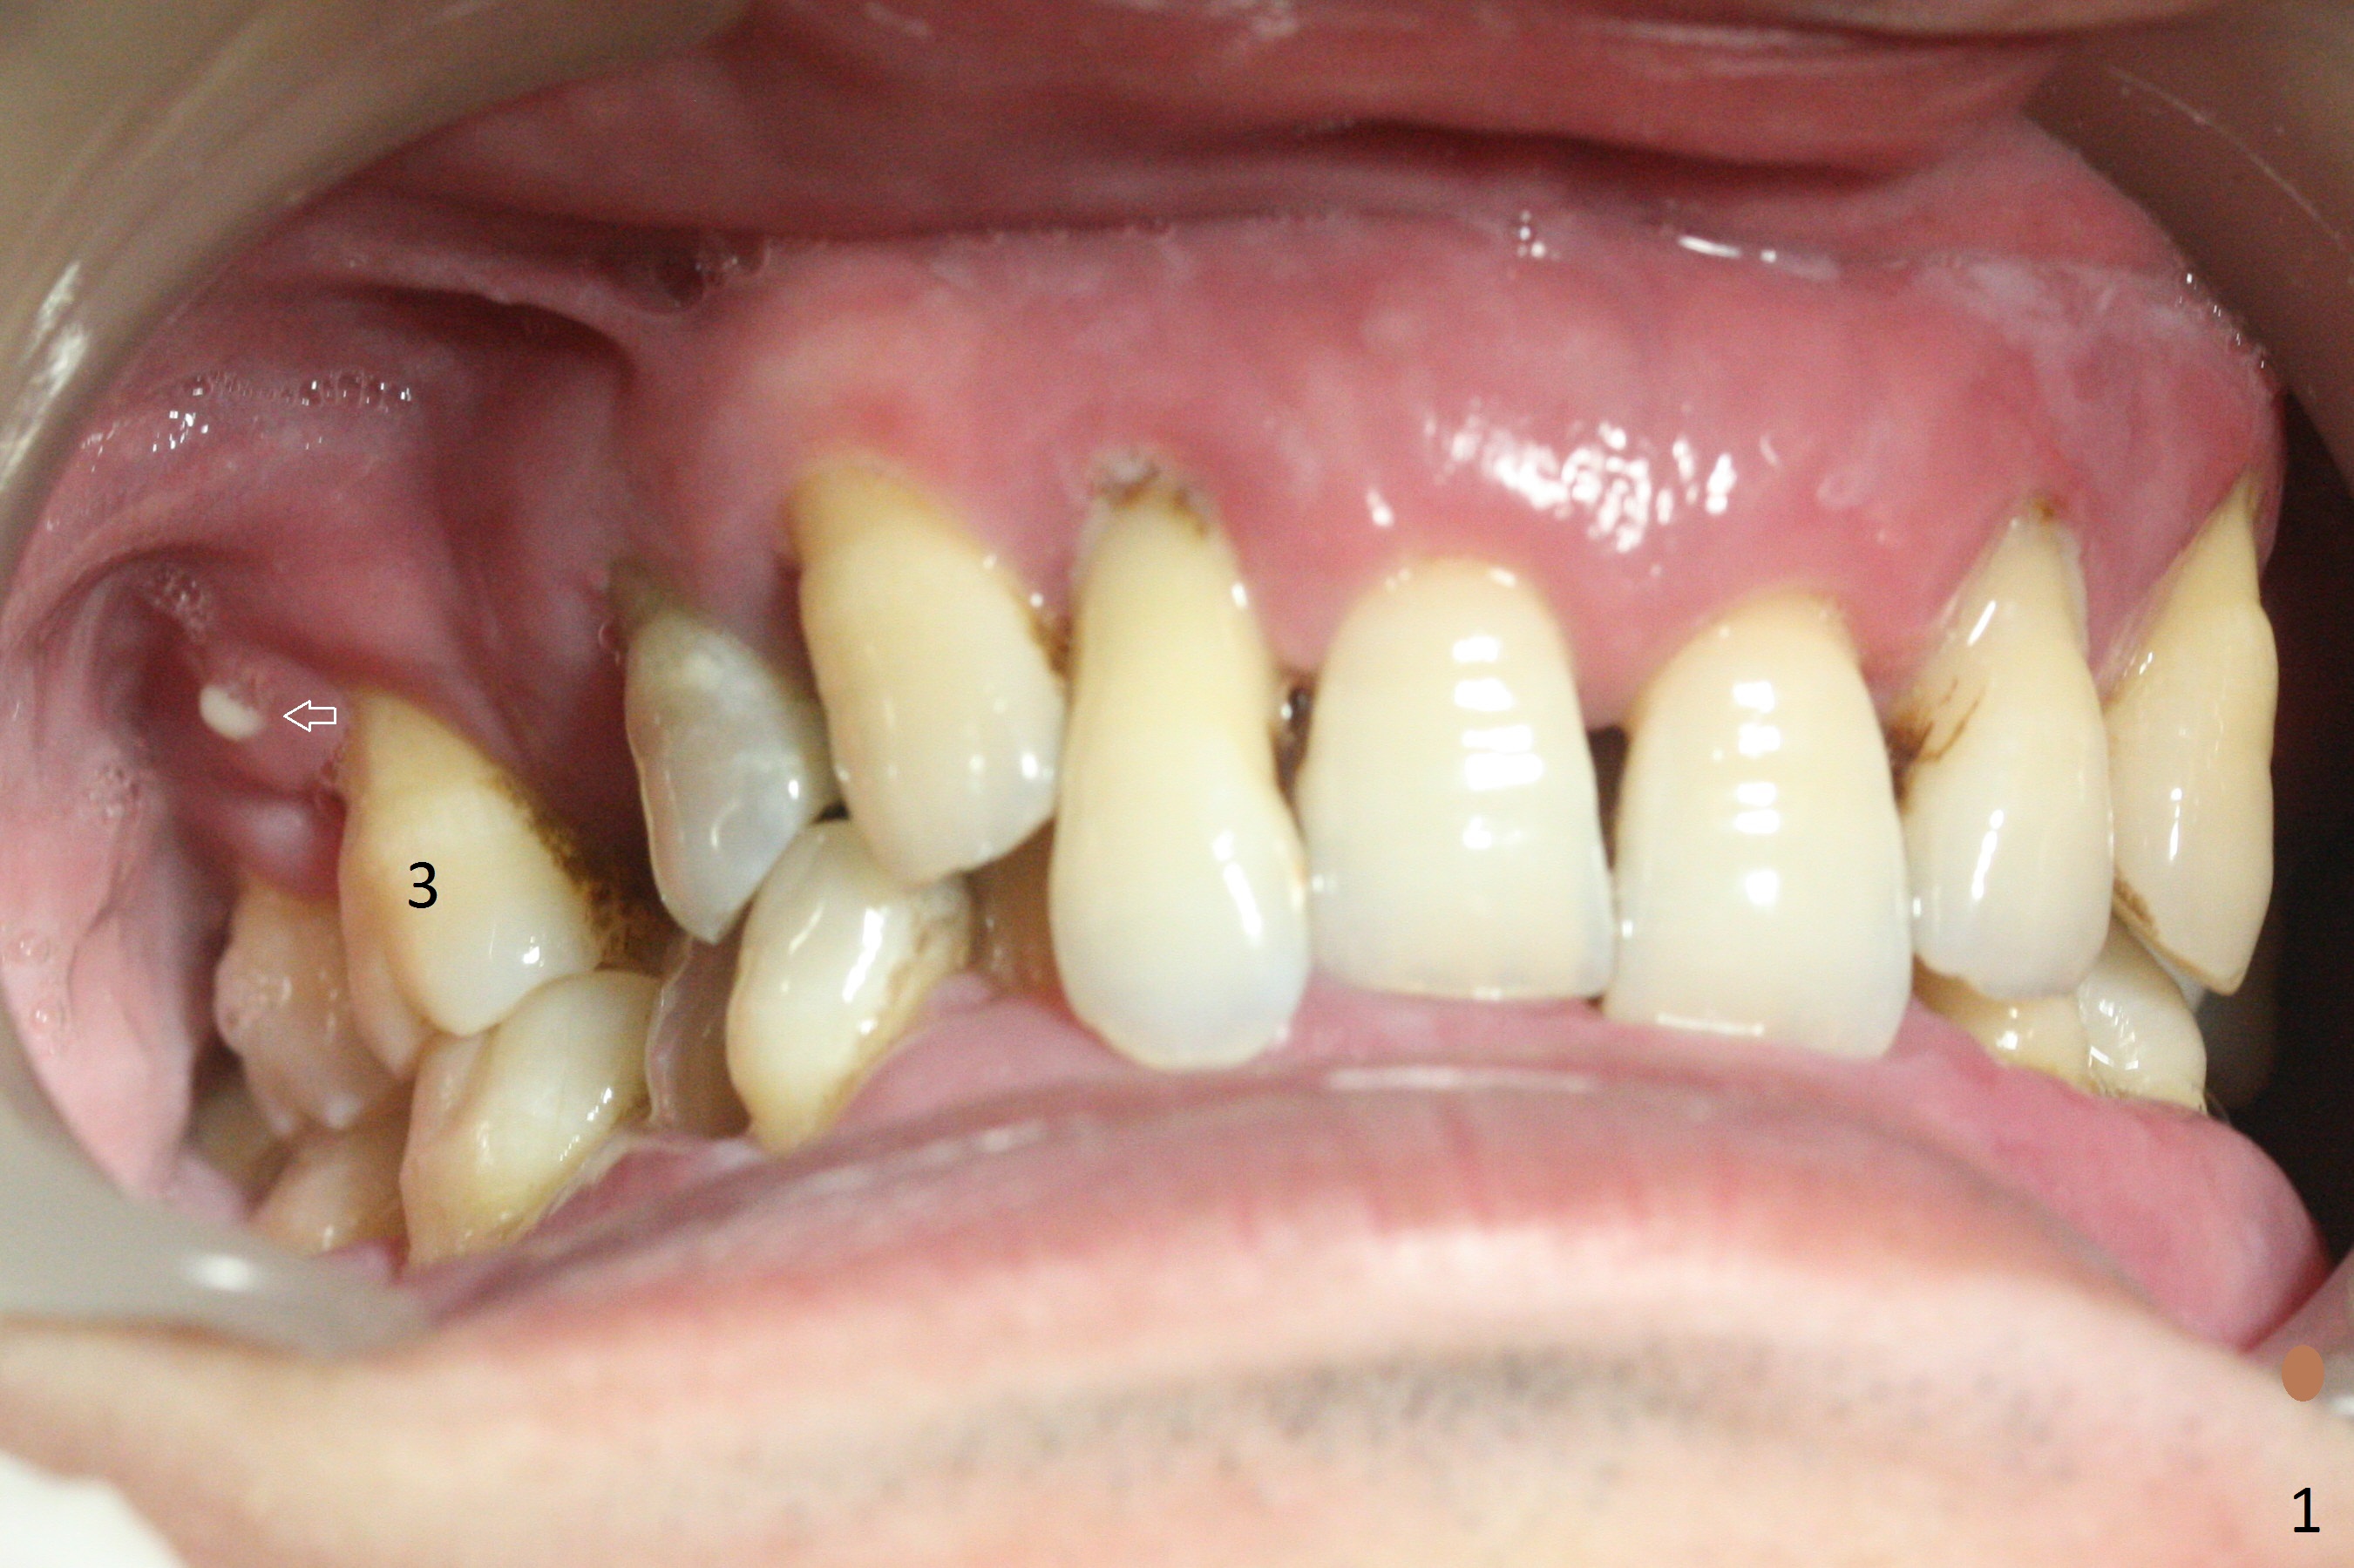

A 36-year-old man (ex-smoker) has advanced chronic periodontitis (Fig.1-5). His chief complaint is "I cannot chew on the right side now because of pain (Fig.1: #3 abscess <) and the bottom front teeth are loose (Fig.2,5: #23-26)". He has not masticated on the left side because of the mobile teeth. Due to finance, implants will be placed at #3,4 (Fig.12), 23 and 26 at the appointments of scaling & root planing.

Class II Division II malocclusion (Fig.2,6) will make it difficult to restore #23-26 implant-supported FPD. Although the teeth #7-10 may need to be replaced later (Fig.7,8), enameloplasty will be conducted for #7-10 (Fig.9 white area; Fig.12 black circles (gross reduction)) prior to #23-26 extraction and implant placement (Fig.10). To be flexible in restoration (angulation) and possible future hybrid denture, 2-piece narrow implants will be placed (3.0 or 3.3 mm) instead of 1-piece ones. In fact CBCT shows that the narrowest regular implant (3.8 mm) can be placed in the lower anterior region (Fig.13-15).